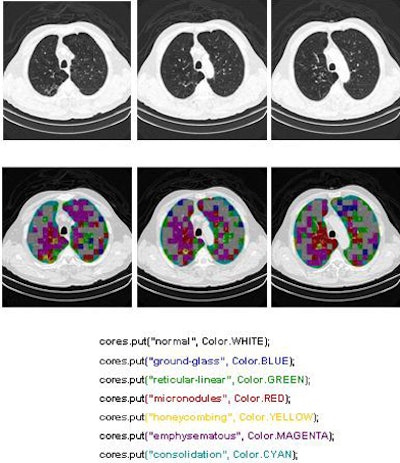

Two of the nine classes, background and outside tissue, indicate regions outside the lungs. The remaining seven classes refer to patterns found in the lungs: normal parenchyma, ground-glass opacities, reticular and linear opacities, nodular opacities, honeycombing, emphysematous change, and consolidation.

In the last step, postprocessing, each pattern type is assigned a color label and the DICOM file is rebuilt. The communication/archiving agent finishes off the process by including the image slices with the labeled ROIs as a new image series in the exam and sending it back to the PACS server. The color coding allows radiologists to easily see which lung regions might be affected by a particular type of diffuse lung disease.

![]() |

| The classification algorithm training and test was performed using a 10-fold cross-validation methodology, which classified regions of interest in the lung parenchyma into nine patterns commonly seen on thoracic high-resolution CT images. The background and outside tissue classes indicate regions outside the lungs, while the remaining seven classes refer to patterns found in the lungs: normal parenchyma, ground-glass opacities, reticular and linear opacities, nodular opacities, honeycombing, emphysematous change, and consolidation. The classification step delivered an initial average accuracy of 61.6% (above). Eliminating the two most frequently confused categories, ground-glass opacities and consolidation, improved the average classification accuracy to 78%. |

| The completed CAD-analyzed cases are stored as a new series in the PACS server, where they can be examined side by side. In the color-coding system, normal parenchyma is white; ground-glass regions are blue; reticular-linear, green; micronodules, red; honeycombing, yellow; emphysematous changes, magenta; and consolidation, cyan. |